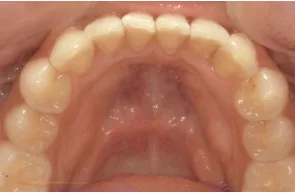

ウィ・スマイルの症例

- 症例1

治療期間 4カ月

治療費 23.1万円(月額1,925円~)

※上顎前歯部、下顎前歯部の叢生をマウスピース型矯正装置で改善したケース。矯正治療上のリスクとして、治療中の虫歯、歯根吸収、歯肉炎 ・歯周炎の発生などが考えられる。